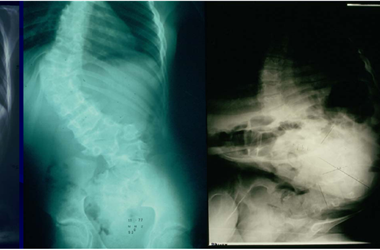

脊柱側彎及治療解決方案

2025-07-10

典型的脊柱側彎包括三維的脊柱和肋骨畸形,根據度數的變化,脊柱從側面彎曲,有時椎骨有輕微旋轉,導致髖部或肩部出現不平衡。